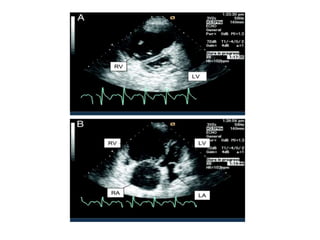

Diagnostico de HAP

• PAPm > 25 mmHg

• PWP < 15 mmHg

• RVP > 3 U W